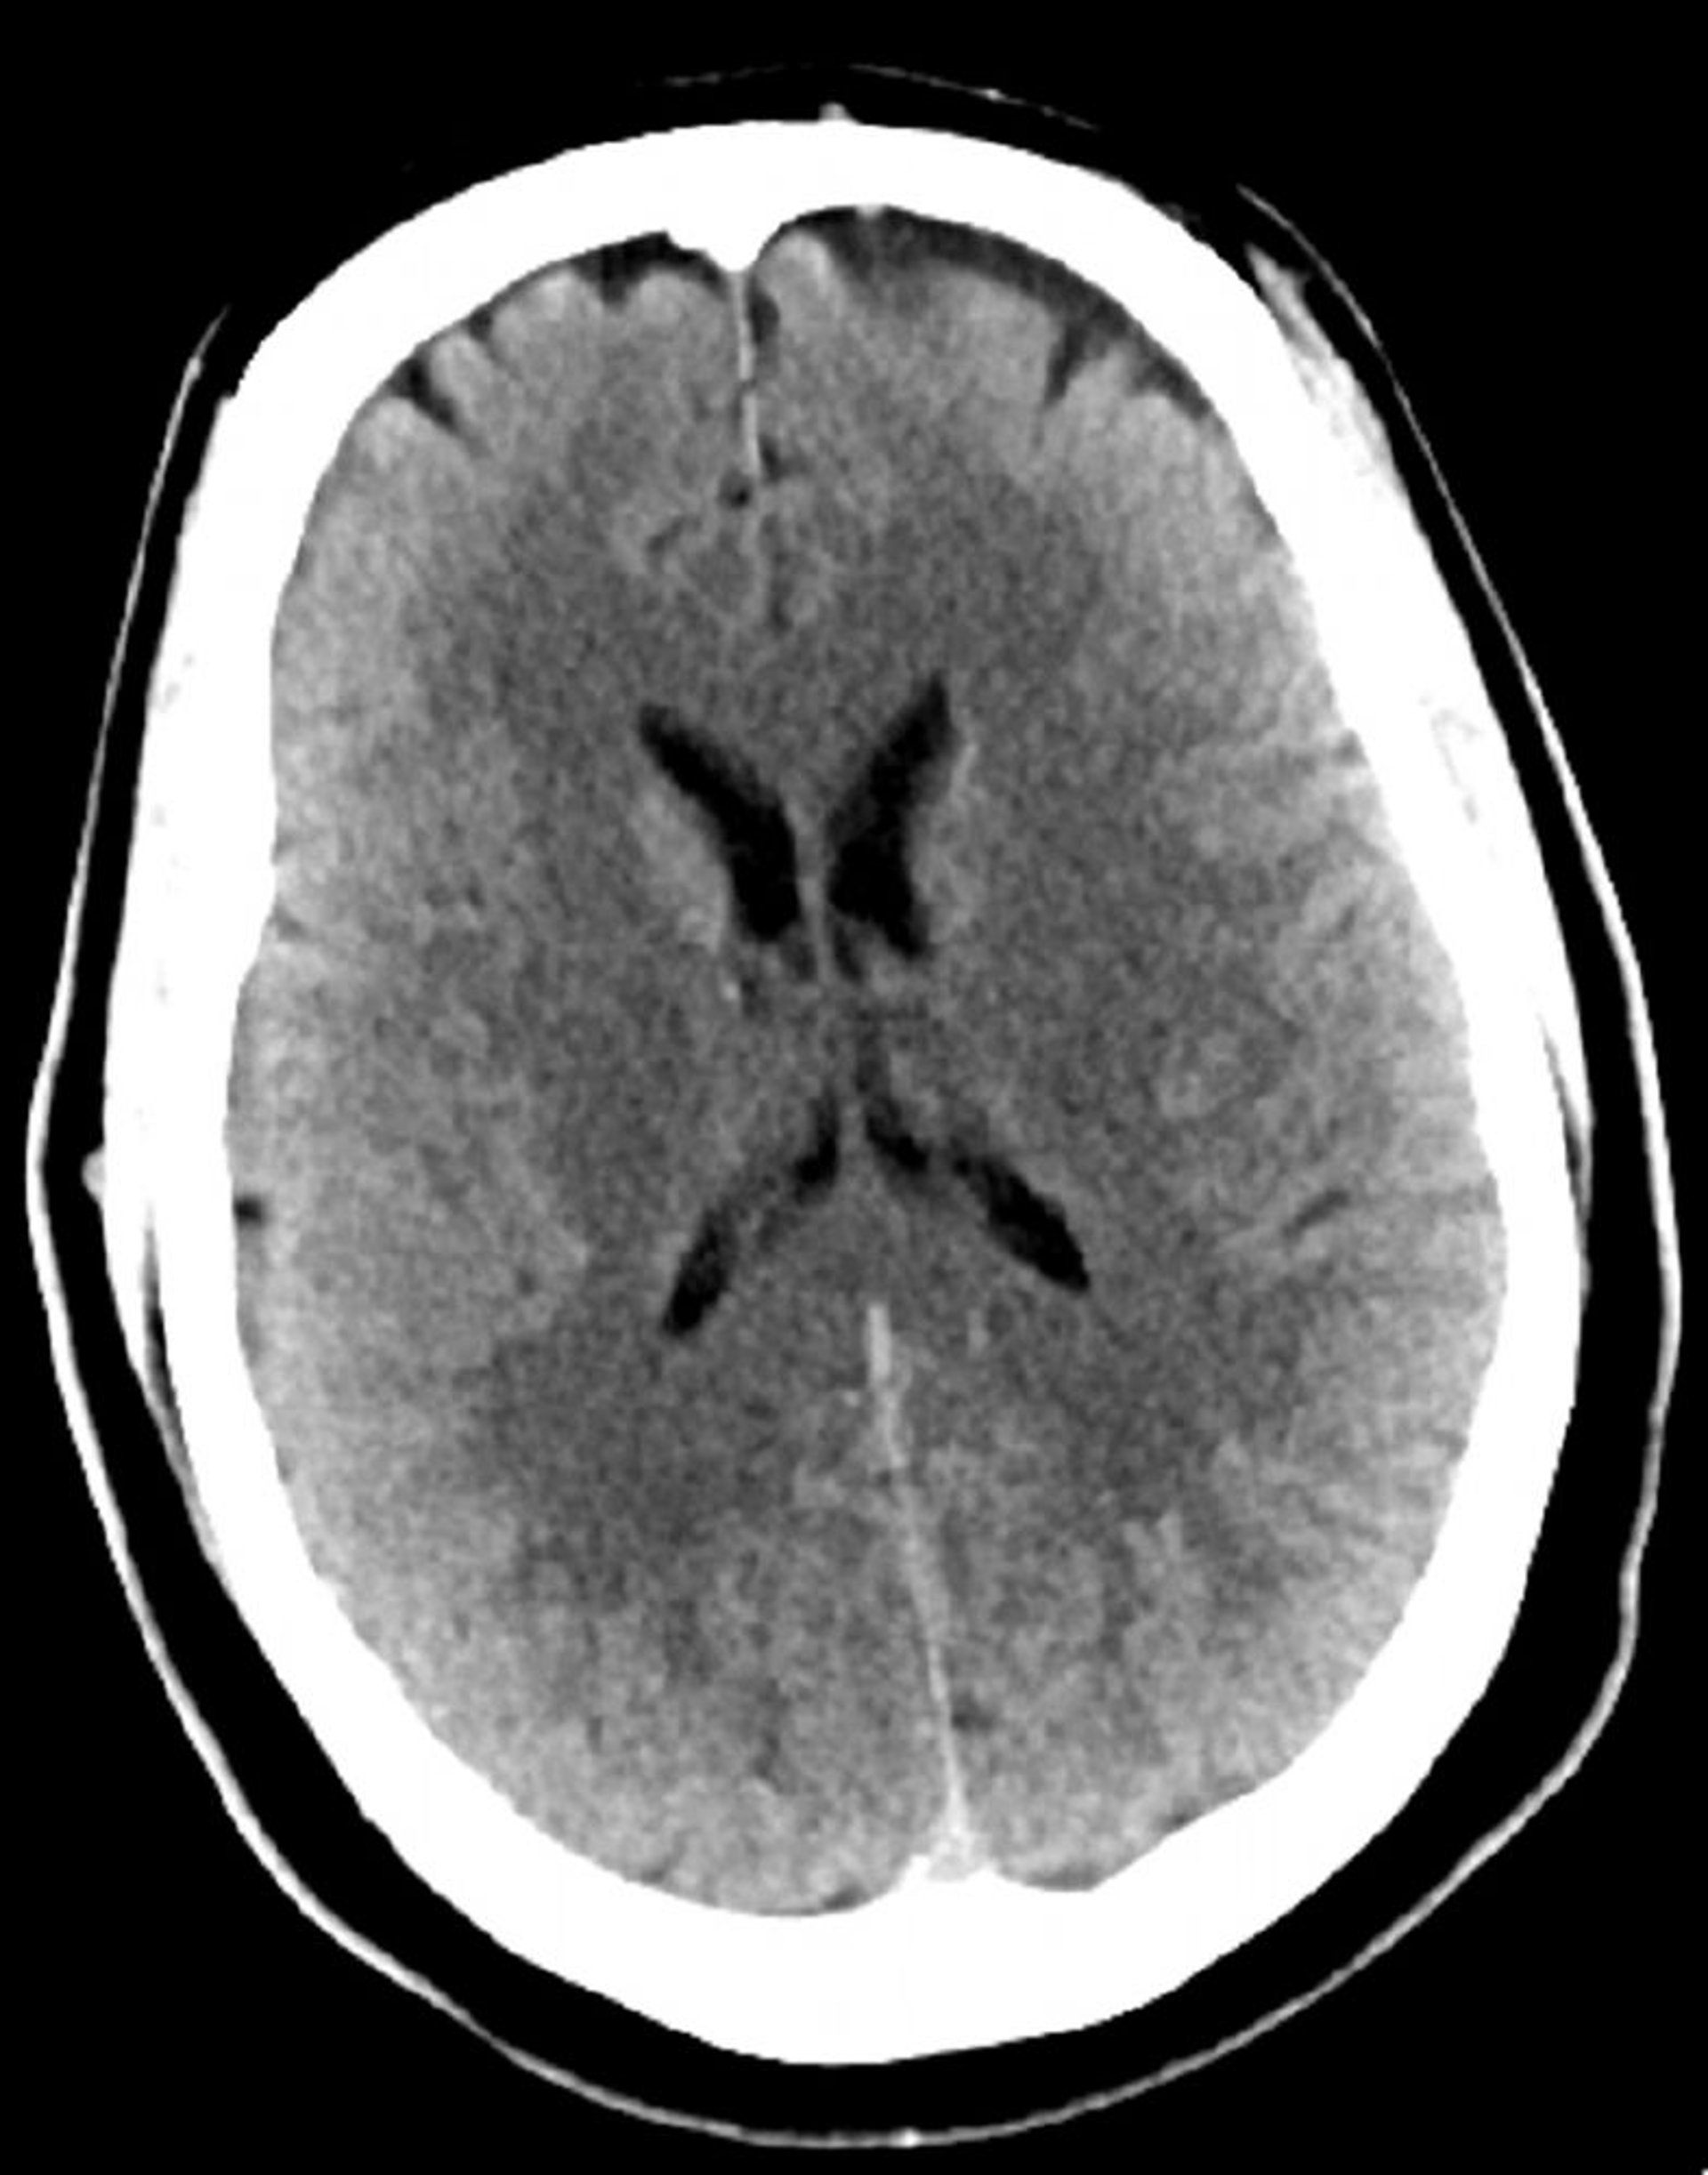

Normal Head CT Scan (Adult, Age 30) – Slide 4

This image is a normal CT scan of the head of a young adult aged 30. There is no intra- or extra-axial fluid or hemorrhage. Grey-white differentiation is preserved. Ventricular size and sulcal pattern are normal.